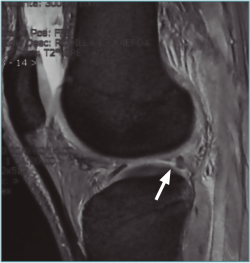

Se considera lesión de la raíz a la avulsión de la misma del hueso con o sin fragmento óseo (Figura 1), o bien a la rotura (normalmente radial) de la región adyacente al mismo (< 1 cm) (Figura 2)(3). Esta puede ser de naturaleza degenerativa o traumática (generalmente asociada a lesiones ligamentosas de la rodilla).

Figura 1. Avulsión de la raíz posterior del menisco lateral (ML) con fragmento óseo (flecha: fragmento óseo avulsionado).